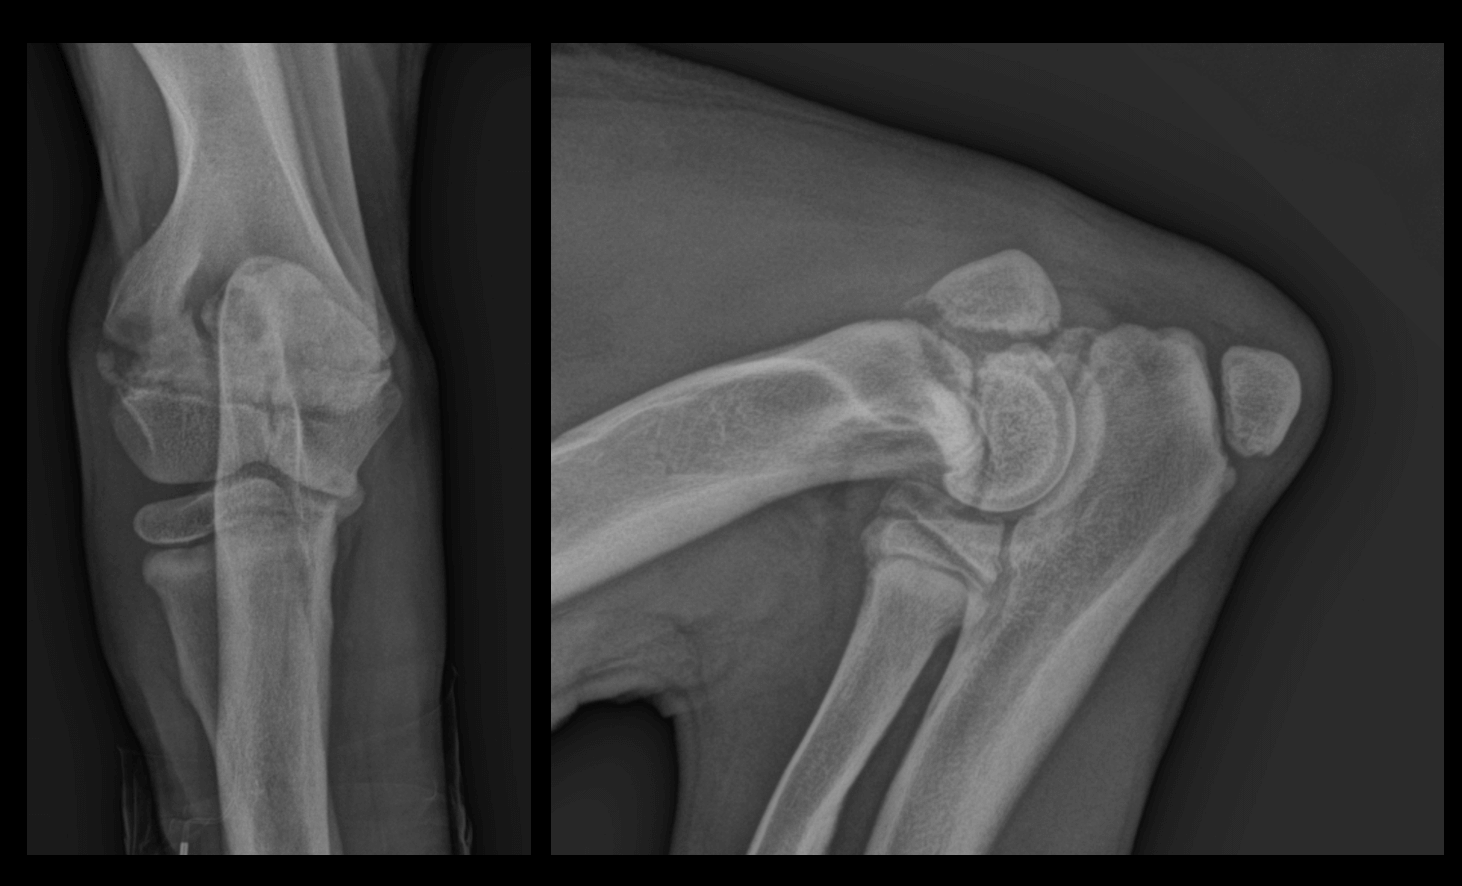

- L'examen radiographique, qui est crucial pour confirmer le diagnostic.

Les radiographies révèlent des signes pathognomoniques, notamment une ligne radiotransparente dans la métaphyse, parallèle à une zone étroite de densité accrue immédiatement adjacente à la physe. Il est important de noter que ces changements radiographiques peuvent ne pas être visibles avant 48 à 72 heures après l'apparition des premiers signes cliniques.Dans les stades plus avancés, on peut observer une prolifération périostée et endostée, ainsi qu'un élargissement excessif des métaphyses, créant un aspect caractéristique en "collerette" osseuse.Le diagnostic différentiel doit inclure l'hyperparathyroïdie nutritionnelle secondaire, la polyarthrite septique, les traumatismes, les noyaux cartilagineux retenus et l'ostéopathie hypertrophique.

Sclérose au niveau de la métaphyse du radius et de l'ulna

Mise en évidence d'une ligne radio-transparente irrégulière en regard de la métaphyse, longeant le cartilage de croissance et séparée de celui-ci par une bande radio-opaque.